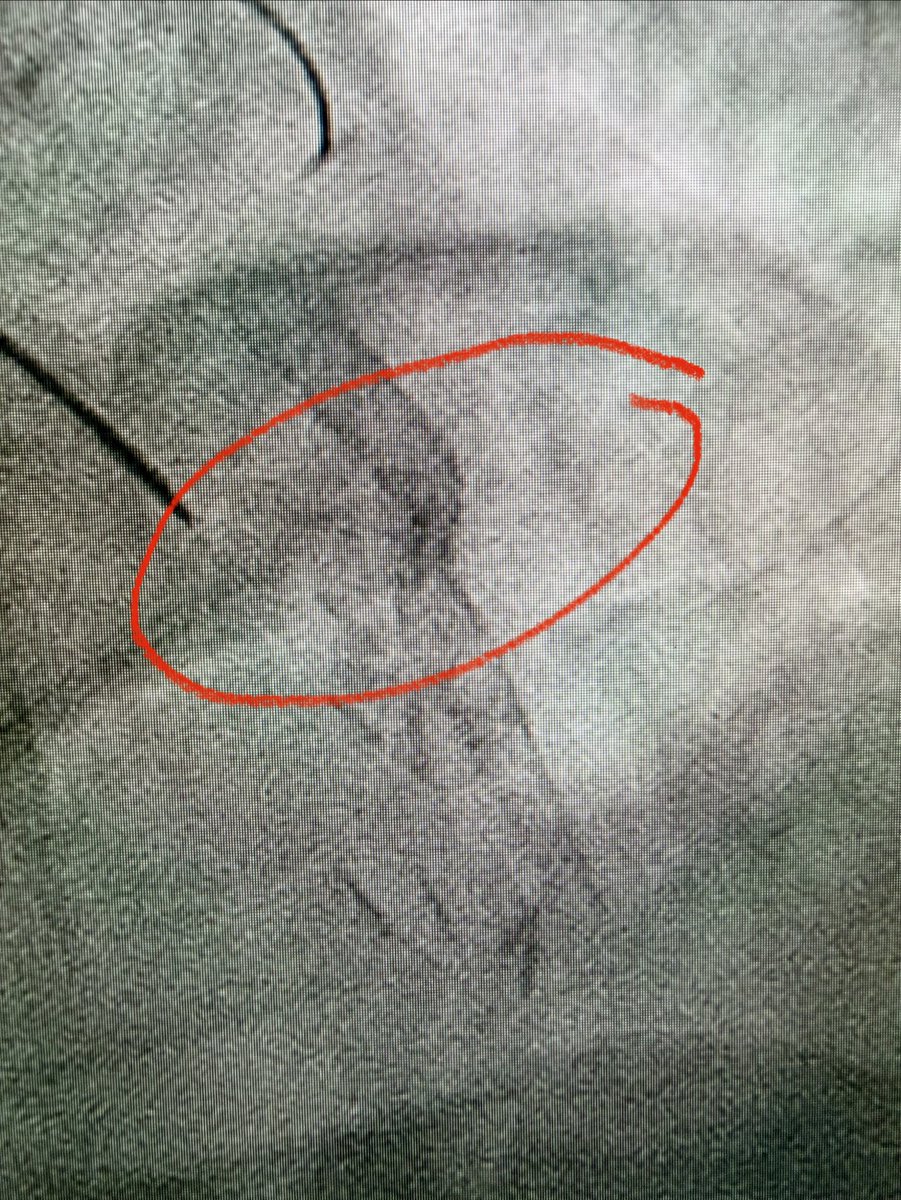

CTO LAD 🔹Dual injection 🔹RCA with wire protection 🔹LAD with microcatheter 🔹Trapping technique to secure the wire 🛑 Always secure the donor first 📍 Microcatheter = Stability + Roadmap ⚠️ Don’t rush the setup, good prep = smoother case 😁 Happier than the patient. #CTO…